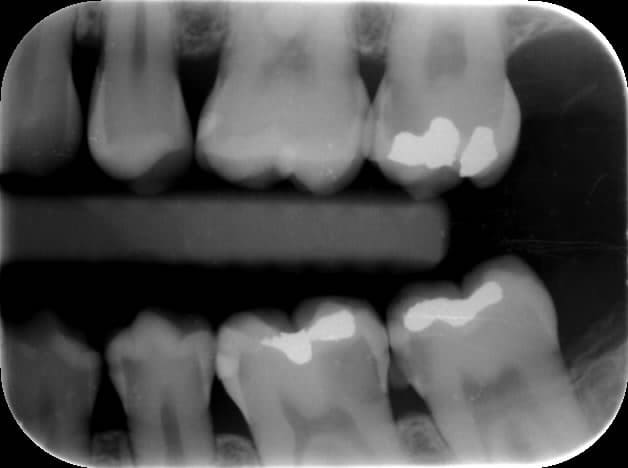

Patiente de 25 ans , 36 sensible au sucre ,et froid .Le praticien consulté fait un devis dévitalisation,inlay core,ccm ...(il avait vu la patiente il y a 2 ans et avait réalisé 2 ccm sur inlay core après dévitalisation de 46.45 : de beaux traitements et belles réalisations par ailleurs mais les caries de l’autre coté devaient déjà être visibles radiologiquement ,non ? )

vu la rx, c'est vrai qu' après eviction de la carie, il y a des chances d'etre tres proche du nerf voir dedans.

La réaction aux stimuli thermiques est transitoire,pas de douleurs spontanées : à priori c'est une pulpite réversible .Une proximité pulpaire justifie t'elle la dévitalisation ?

Ce qui est un peu bizarre c'est de parler déjà d'inlay-core (mais ici on n'a que des radios, pas de photos de la cavité après éviction carieuse), alors qu'on n'est même pas encore sûr que l'endo soit nécessaire...

a voir aprés éviction totale de la carie si pas d'effraction de la pulpe et substance restante suffisante dentine/email.

La radio est une pale indication.

Tout à fait mais ce qui me genait c'est que les caries secteur 3 n'aient pas été détectées .